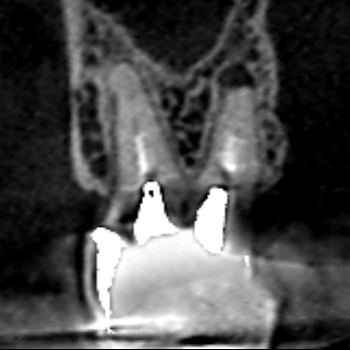

精密根管治療6カ月後の経過観察時の冠状断のCT画像です。上顎第二大臼歯の口蓋根の先にみられた膿の影が縮小し歯槽骨が再生しています。